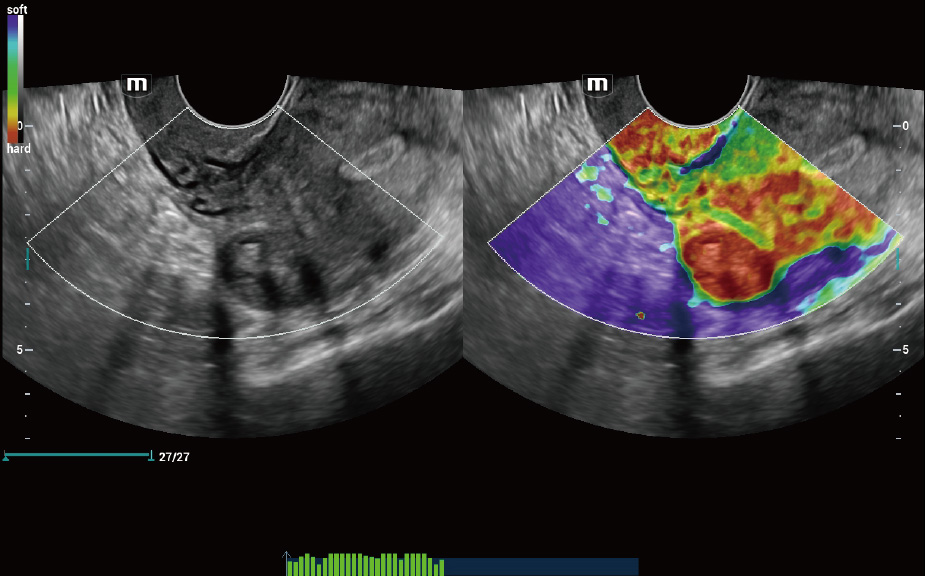

Con tecnologia ZST+

La piattaforma ZST+ rappresenta uno straordinario balzo in avanti nella tecnologia degli ultrasuoni, passando dal beamforming convenzionale all'elaborazione dei dati di canale. Questa innovazione rivoluzionaria supera i tradizionali compromessi tra risoluzione spaziale, risoluzione temporale e uniformit├Ā dei tessuti, dando vita a una qualit├Ā d'immagine senza pari che consente infinite soluzioni di imaging.

Intelligenza completa orientata allo scenario clinico

L'innovativa soluzione Smart Scene 3D consente l'identificazione automatica delle caratteristiche dei tessuti e fornisce una diagnosi specifica per i diversi distretti di esame durante l'intera procedura. Questa innovazione aumenta lŌĆÖaccuratezza e la sicurezza diagnostica, migliorando lŌĆÖefficienza.